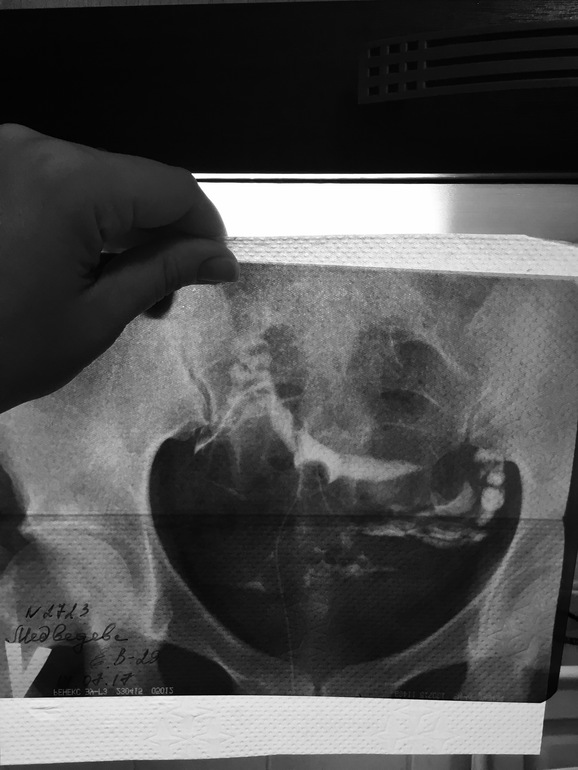

узи мне ре делала, ничего не сказала. А когда сделала мсг, в заключении прочитала: Трубы проходимы, матка смещена вправо.

А у меня про матку не слова, хотя на снимке это видео чётко...я хз как они заключения пишут...

я на своем снимке вообще ничего не вижу, муть только какая то